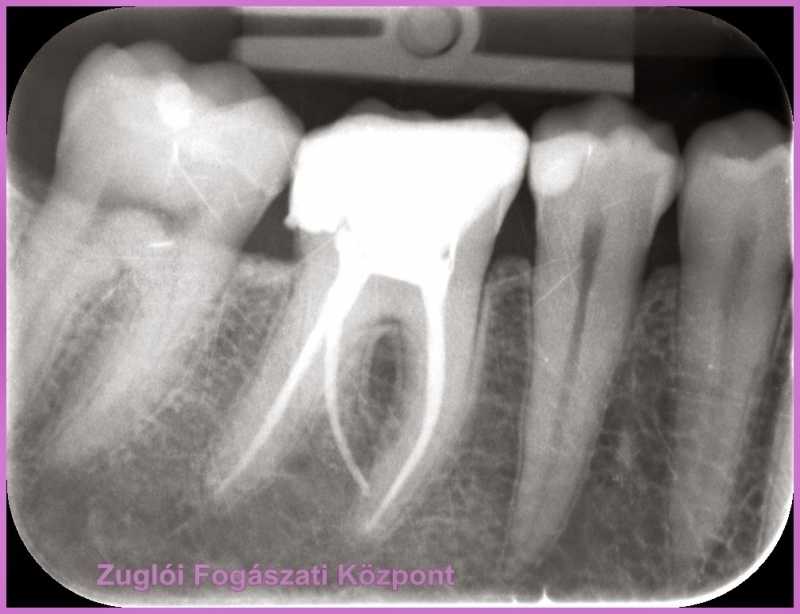

A jobb első nagyőrlőről készült röntgenkép alapján a hölgyet először Dr. Molnár Katalin gyökérkezelés-szakértőnkhöz irányította.

röntgen alapján gyökér kezelni kellett a fogat